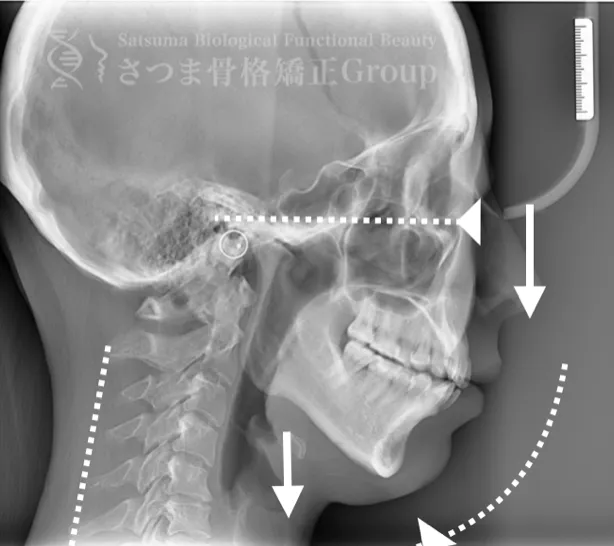

これらの問題を正確に評価するため、当院では セファロシステムによるレントゲン撮影(X-ray images) を行っています。

セファロ撮影によって 顎関節・頭蓋骨・頸椎の位置関係を客観的に可視化でき、施術前の状態を科学的に把握することが可能となります。

施術の前後で撮影したレントゲン写真を比較することで、改善の度合いや変化を一目で確認できます。